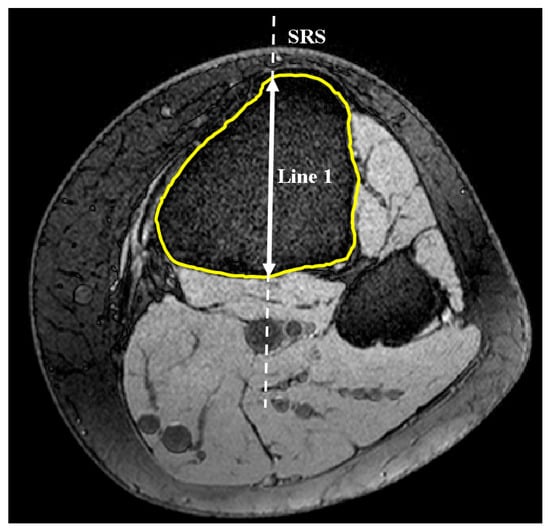

2.1. Medial and Lateral Tibial Slope Measurement Methodology